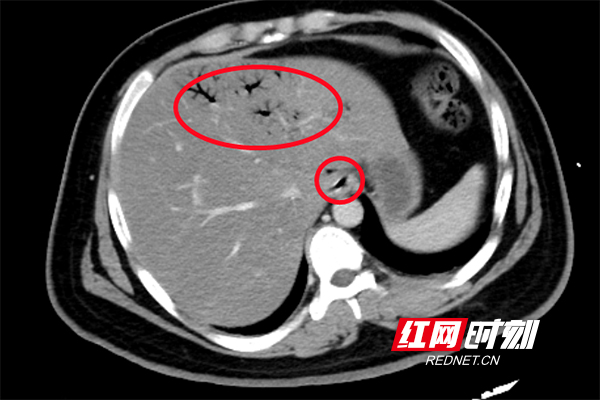

CT显示,肝脏血管内有明显积气(红圈内)。

进入急诊三科抢救室时,小刘已经神志浅昏迷,呼吸急促,脉搏高达145次/分,血压低至休克,快速血糖检测高到“爆表”,只得抽血测血糖,结果显示为123.10mmol/L,超出正常值20多倍!此外,感染指标明显升高;腹部CT显示:左肝静脉、门静脉、肠系膜静脉及小肠壁积气明显,考虑小肠坏死,随即转入EICU。

“门静脉和肠系膜静脉等出现积气是因为产气细菌进入血液,这种情况在影像学上被称为‘死神之征’,死亡率高达50%”,张兴文表示,小刘由于不良生活方式导致体重超标,并患上糖尿病,在此之前一直没有规范治疗和改变不良生活方式,这次因为肠道菌群失调、移位出现肠源性感染,引发感染性休克,最终导致严重的糖尿病酮症酸中毒(DKA),危及生命。